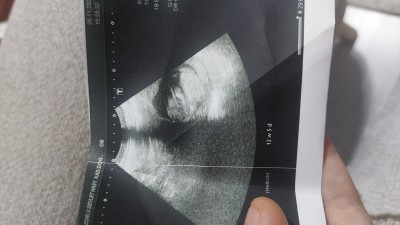

Çöl belli değil ama sizce cimsiyet tahmini edermisiniz

Gebelik haftası 13.6

Kız hissettim  sağlıkla olsun